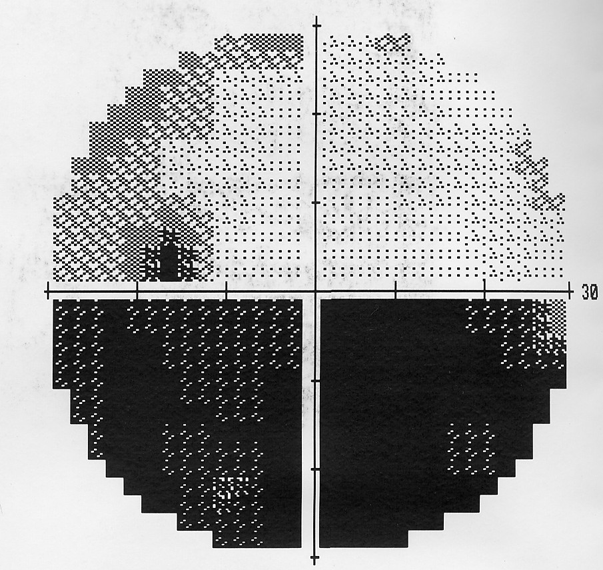

急性期非動脈炎性虚血性視神経症の視野

典型的な水平下方神経線維束欠損型視野欠損